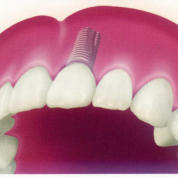

Einzelzahnlücke

Eine

klassische

Indikation

für

Implantate

ist

bei

Verlust

eines

einzelnen

Front-

oder

Seitenzahnes

gegeben.

Hierbei

wird

der

fehlende

Zahn

durch

ein

Implantat

ersetzt

und

anschließend

mit

einer

vollkeramischen

Krone

hochästhetisch

versorgt.